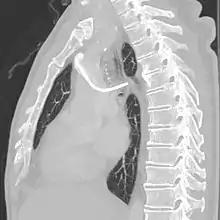

After the entry site is punctured with ultrasound, a guidewire is inserted with the tip of the guidewire reaching the inferior vena cava. The proximal end of the guidewire is secured to prevent dislodgement. Then a chemoport pocket is created on the deltopectoral region at 2.5 cm below the level of clavicle by using a scalpel. Bupivacaine with adrenaline (0.25%) is used as local anesthetic to reduce the formation of haematoma and prolong the anesthetic effect. After the pocket is created, a trocar is used insert a silicone catheter from the pocket towards the internal jugular vein puncture site. A peel-away sheath is then inserted to facilitate the insertion of the silicone catheter into the cavoatrial junction. Silicone catether insertion should be done during breath hold at inspiration. The peel-away sheath should be pinched to prevent air embolism. The proximal end of the catheter is connected to the port within the skin pocket later after irrigation of the pocket with normal saline.[3]

The port is then sutured on two sites to the underlying muscles. The tip of the catheter is checked for kinks and position using a fluoroscope. Besides that, aspiration of blood and contrast injection through the chemoport can also be used to confirm the position. The port is the closed in two layers (subcutaneous tissue is sutured first, followed by the skin). Sterile dressing is then placed on the port.[3] The optimum site to park the tip of the catheter is at the cavo-atrial junction or with margin of error of not more than 4 cm above the junction.[3]

The incidence of catheter fracture is 2.3%. The fracture can be due to "pinch-off syndrome" when the vein and the catheter is compressed when passes between the clavicle and first rib before turning 90 degrees into the superior vena cava. Fractured catheter component can dislodge most commonly into pulmonary arteries (35%), right atrium (27%), right ventricle (22%), and superior vena cava and peripheral veins (15.4%).[5]

Malpositioning of the catheter happens in 0.1 to 5.6% of the time. This can be due to malposition within or outside the superior vena cava. Causes includes: unexpected branches of the veins, vessel angulations, vein stenosis or venous tortousity.[5]